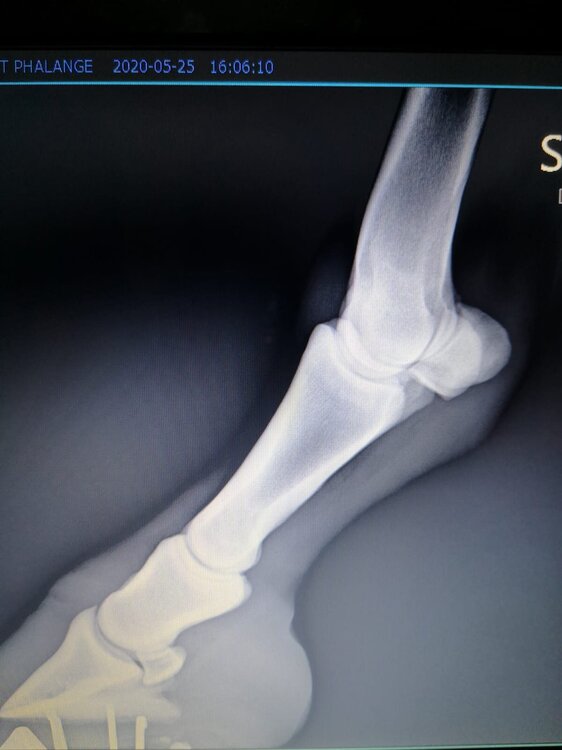

Salve volevo chiedervi qualche informazione in merce tò a un problema che ho avuto con la mia puledra. Qualche settimana fa mentre stavo lavorando alla corda è scivolata urtato l'arto posteriore sinistro. Arrivati in box ho messo dell'acqua a pressione perché si era gonfiato sia il nodello sia il pastorale. Già l'indomani l'arto era sgonfio ritornato normale, quindi ho continuato a lavorarla. Ma dopo qualche giorno di lavoro alla corda leggerissimo, al rientro in box ho notato che sia il nodello che il posturale gonfiavano nuovamente. Allora ho chiamato il veterinario che ha detto che la cavalla aveva una lussazione e mi ha insegnato come cura una fasciatura con della creta per 24h per cinque giorni e un antinfiammatorio. Dopo un paio di giorni la fasciatura ha fatto come delle vesciche e il gonfiore è aumentato dal pastorale alla garra. Abbiamo chiamato un altro veterinario abbiamo fatto vedere anche a lui la cavalla e diceva che poteva essere la frattura del ditino, ma si dovevano fare le lastre per essere sicuri. Ora abbiamo fatto le lastre e il radiologo dice che c'è dell'infiammazione ma non c'è niente di grave. Il veterinario,viste le lastre dice che deve essere operata. Allora abbiamo consultato un'altro veterinario che dice che la cavalla non ha assolutamente niente. Ora io vi allego le radiografie, datemi un vostro parere perché non só più cosa fare. Grazie